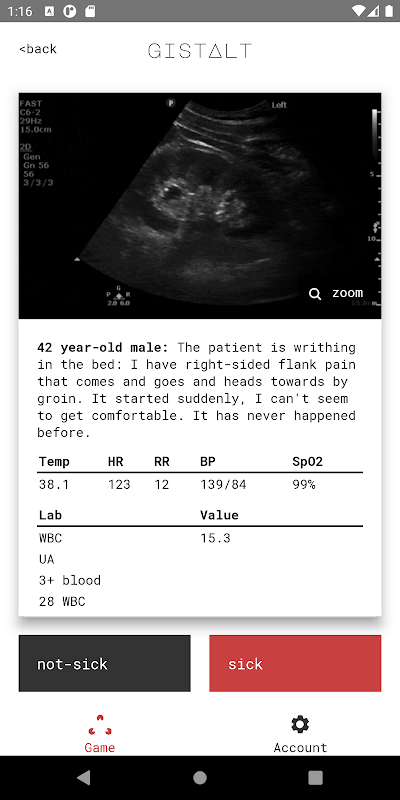

Il tuo obiettivo giocando a gistalt è identificare accuratamente quali pazienti sono malati (che richiedono ricovero in ospedale o interventi immediati per la stabilizzazione) o non malati (condizioni che possono essere trattate in sicurezza con un follow-up ambulatoriale).

i giochi gistalt sono semplici e divertenti. Inizierai con una serie di presentazioni dei pazienti, inclusi i segni vitali, i risultati di laboratorio e l'imaging. Scorri ogni scheda a sinistra (per non malato) oa destra (per malato) per vedere la domanda successiva. Alla fine della pila, rivedi le tue risposte e guarda il tuo punteggio. Il tuo punteggio gistalt misura in modo speciale la tua capacità di rilevare i pazienti più critici e di istituire i trattamenti che faranno la differenza.